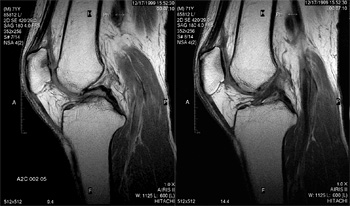

■ オープン型MRI装置

低音・開放・高速の最新の日立MRI装置を設置しております。

ワイドオープン型のシステムですので、圧迫感・閉塞感が少なく、小児やご高齢の方でも安心して検査が受けられます。

音が静かなMRI装置です。

画像は(株)日立メディコのHP(http://www.hitachi-medical.co.jp/product/mri/com/index.html)より引用